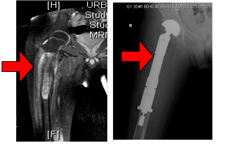

(1) 肢體保留手術目前有兩種方法:一種是將長了腫瘤的關節整個換掉,用訂製型人工關節替代(圖一);另一種是使用他人捐贈的骨骼,取代原來切除的部份(圖二)。

圖一、一位七十二歲男性患者,患有右側股骨腫瘤。經廣泛腫瘤切除後,使用訂制型人工關節,一方面可以保留肢免於截肢,一方面也可以保留肢體功能。

圖二、二十四歲男性,患右側肱骨惡性骨肉瘤,經廣泛腫瘤切除,使用他人捐贈之骨骼,重建肢體功能。